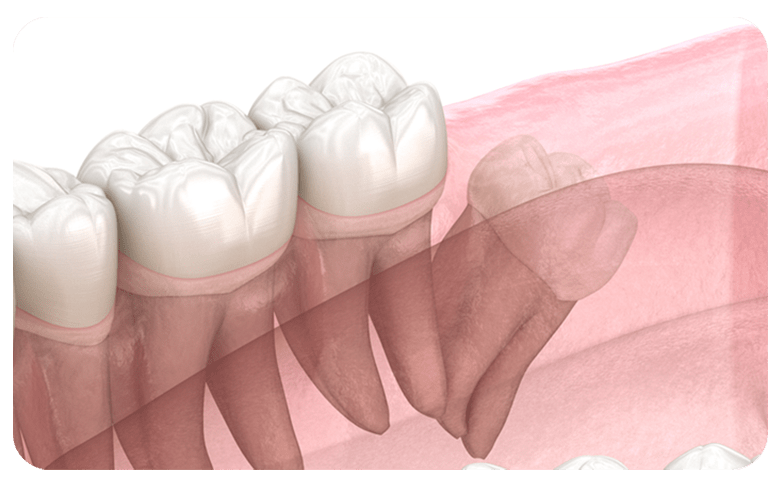

매복사랑니란?

사랑니가 완전히 맹출 되지 않고 잇몸 아래에 묻혀있는 형태의 사랑니를 매복 사랑니라고 합니다.

매복 사랑니는 함치성낭종, 염증 유발, 턱뼈 손상 등의 문제를 유발할 수 있어 발치해주는 것이 좋습니다.

수직매복

수평매복

부분매복

원심경사 매복